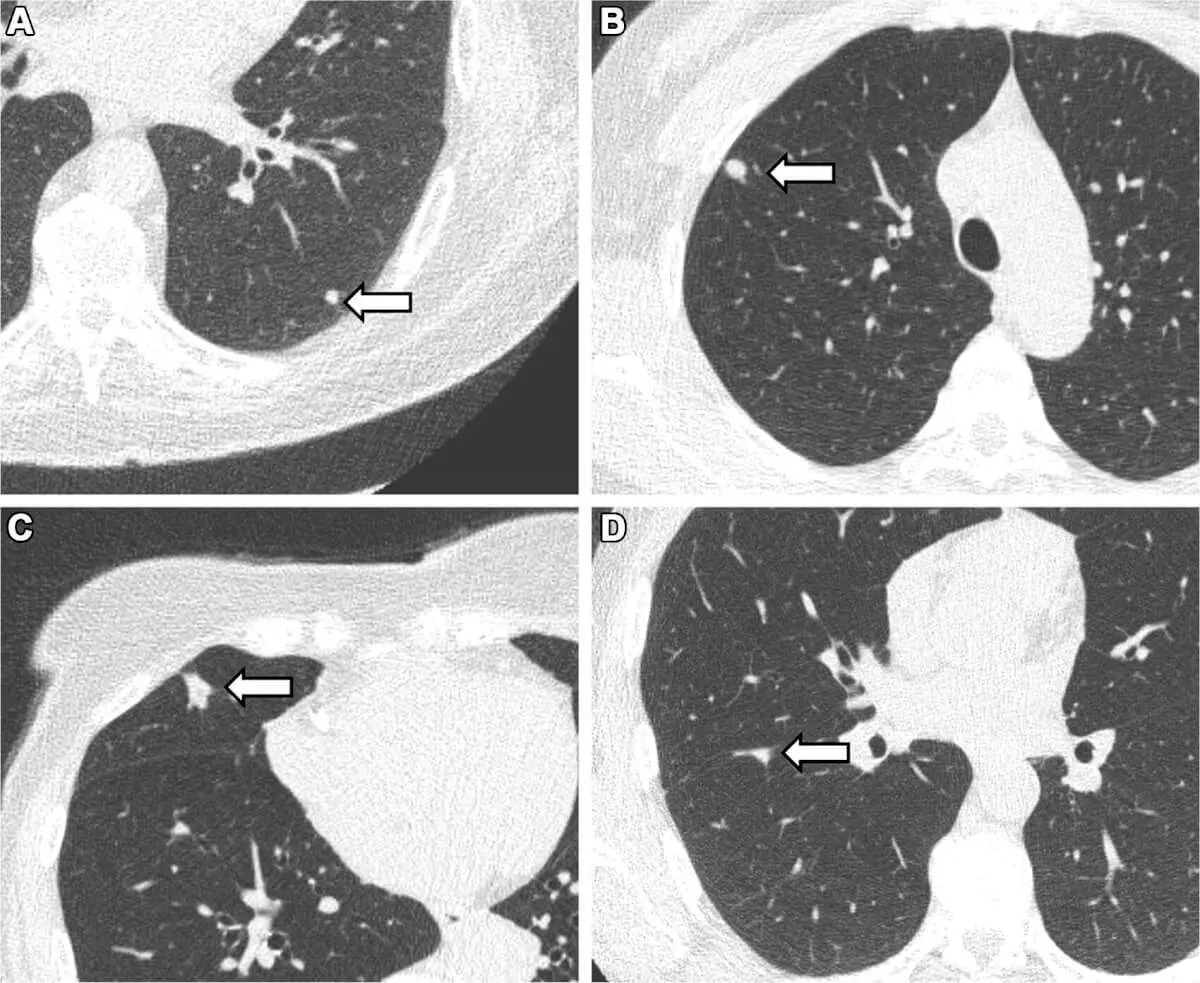

به نقل از اس‌اف، گرهک‌های ریه ساختارهای کوچک و گردی در بافت ریه هستند. در حالی که بیشتر آنها خوش خیم هستند، برخی می‌توانند نشانه‌های اولیه سرطان ریه باشند. به طور سنتی، این گرهک‌ها با سیگار کشیدن مرتبط بوده‌اند و بیشتر درک ما از شیوع آن‌ها از مطالعات افراد به شدت سیگاری‌ یا افرادی که در معرض خطر بالای سرطان ریه هستند، ناشی می‌شود.

در این مطالعه بیش از ۱۰ هزار شرکت‌کننده از شمال هلند حضور داشتند که همگی یا قبلا سیگاری بودند یا هرگز سیگار نکشیده بودند. با استفاده از سی تی اسکن محققان توانستند گرهک‌های ریه را به قطر ۳.۹ میلی‌متر تشخیص دهند.